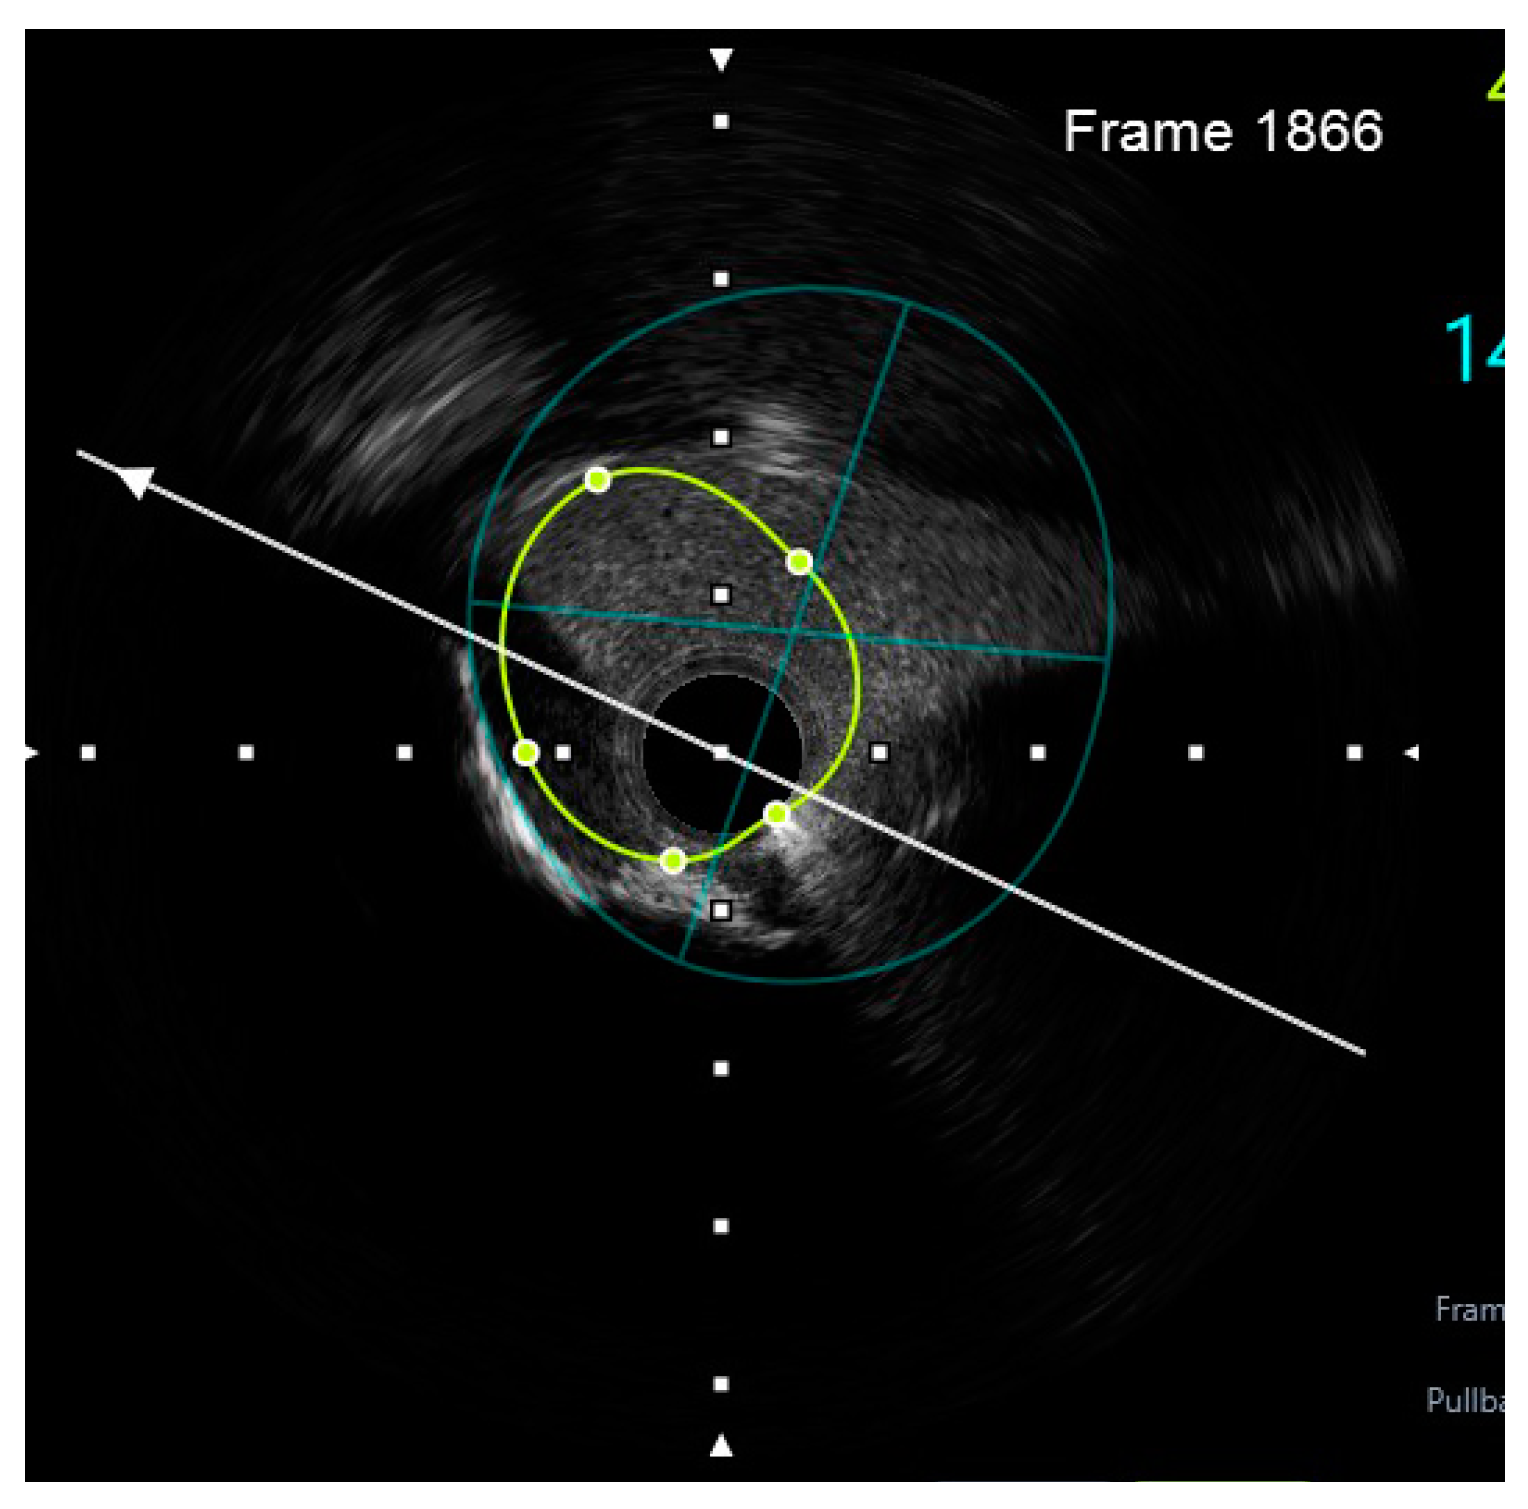

Figure 8.

Preprocedural IVUS LCX. White arrow—axis.Orange circle—vessel area. Blue circle—remaining luminal area.

Finally, intravascular ultrasound (IVUS) revealed adequate expansion with an optimal angiographic result and no periprocedural complications (Figure 26, Figure 27, Figure 28 and Figure 29).